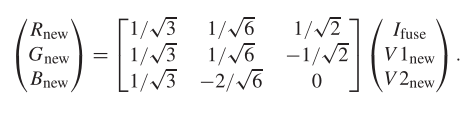

以下公式为RGB与IHS的转换公式

损失函数